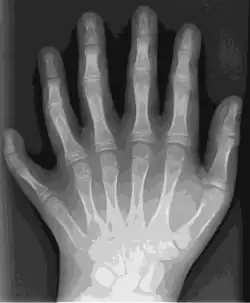

Trazado con Potrace en Inkscape a imagen SVG de ocho colores en 2012 (336 KB) -